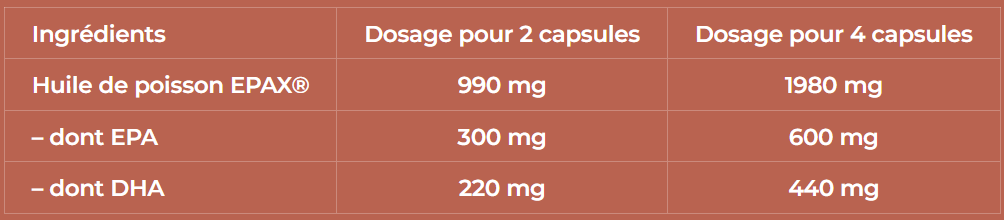

QUELLE EST LA COMPOSITION DE CALCIUM COMPLEXE SANTERRA?

Gélules composées de calcium avec cofacteurs

Sources de Calcium : Pidiolate de Calcium et bisglycinate de calcium TRAAC

Vitamine K2MK7 brevetée : MenaQ7® Matrix

Vitamine D3 naturelle issue de lichen Vitashine®

| Ingrédients | Dosage pour 2 gélules | Dosage pour 4 gélules |

|---|---|---|

| Bisglycinate de calcium | 577 mg | 1154 mg |

| – dont calcium | 150 mg (18,75%) | 300 mg (37,5%) |

| Pidolate de calcium | 389 mg | 778 mg |

| – dont calcium | 50 mg (6,25%) | 100 mg (12,5%) |

| Bisglycinate de magnésium | 166 mg | 333 mg |

| – dont magnésium | 30 mg (8%) | 60 mg (16%) |

| Vitamine K2 (MK7) | 80 μg (106,5%) | 160 μg (213%) |

| Vitamine D3 | 0.5 μg (10%) | 1 μg (20%) |

Ingrédients : Bisglycinate de calcium, pidolate de calcium, tunique : gélifiant hydroxypropylméthylcellulose, bisglycinate de magnésium, ménaquinone-7 (vitamine K2-MK7), antiagglomérant : acide stéarique, cholécalciférol végétal (vitamine D3).